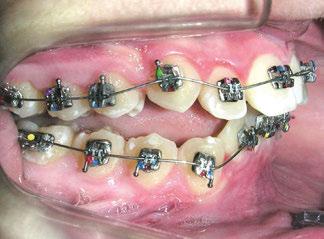

En este artículo se describe el caso de una niña de 9/2 años con síndrome de Clase II por hipoplasia mandibular que recibió tratamiento en dos fases: una primera, ortopédica, para estimular el crecimiento mandibular mediante aparatología funcional; y una segunda fase, ortodóncica, con la colocación de brackets de autoligado pasivo de la técnica USS (Universal Smile System) de prescripción variable para el desarrollo y coordinación de las arcadas dentarias.

La exploración intraoral (figuras 4 a 8) revela una Clase II molar y canina completa, líneas 1/2 dentarias superior 0,5 mm e inferior 1 mm ambas desviadas hacia la derecha, los incisivos superiores excesivamente protruidos y vestibulizados (seguramente debido a la interposición del labio inferior), resalte de 13 mm y sobremordida 2/3 de corona. La discrepancia oseodentaria

inferior es de -3,5 mm y la curva de Spee de 4 mm.

Con el cementado de los brackets de la técnica Universal Smile System

(USS), como se aprecia en las figuras 23 a 25, comienza la segunda fase de tratamiento. Esta duró tan solo 12 meses debido a que gran parte de las relaciones oclusales habían mejorado durante la etapa anterior. Los resultados finales del tratamiento se observan en las figuras 26 a 30 , con la corrección de la clase molar y canina, el resalte y la sobremordida, el centrado de las líneas 1/2 y la curva de Spee. La mejoría en la macro, mini y microestética facial se aprecia en las figuras 31 a 33 , a pesar de la evidente desviación del mentón hacia